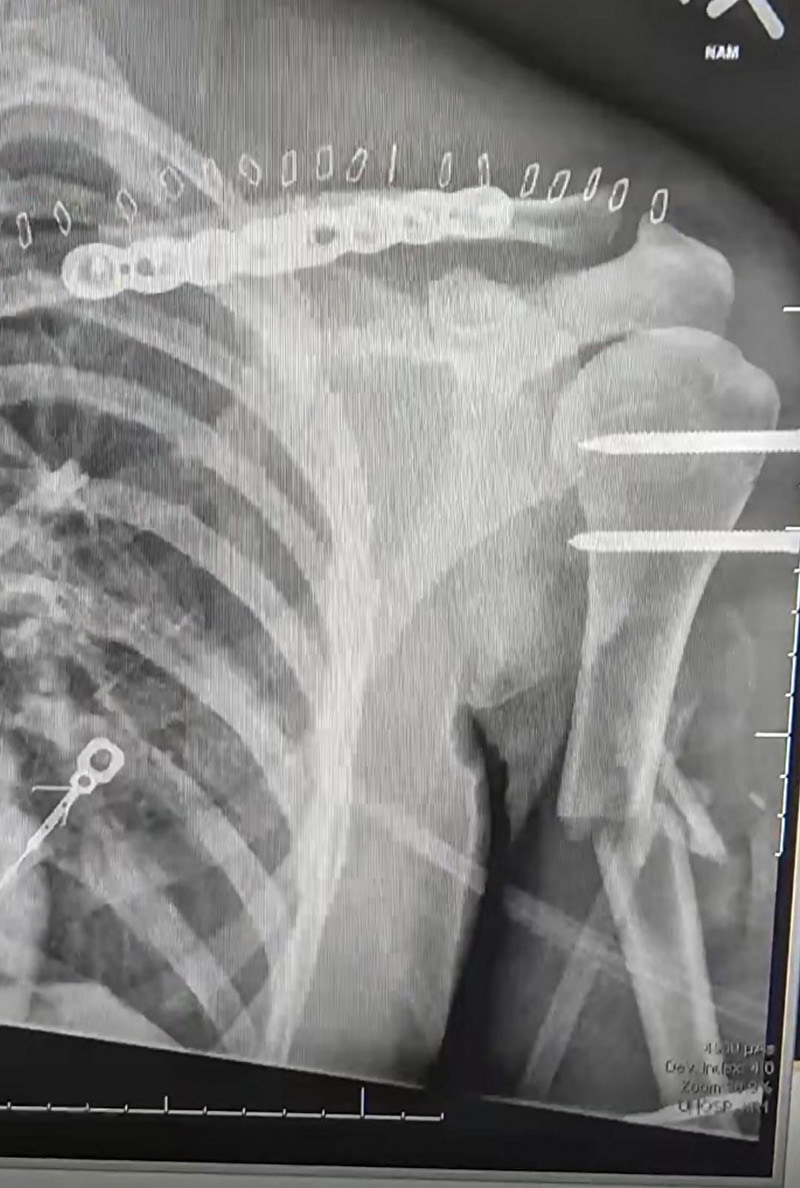

gif_animation アメリカにて、10代の少女が運転する車がクラッシュを起こし激しく横転 → 投げ出され電線に引っかかった状態で発見される、という衝撃画像。更に驚きなのが、彼女は実はまだ生きており、治療の末一命を取り留めたという一連のギャラリー[10]img